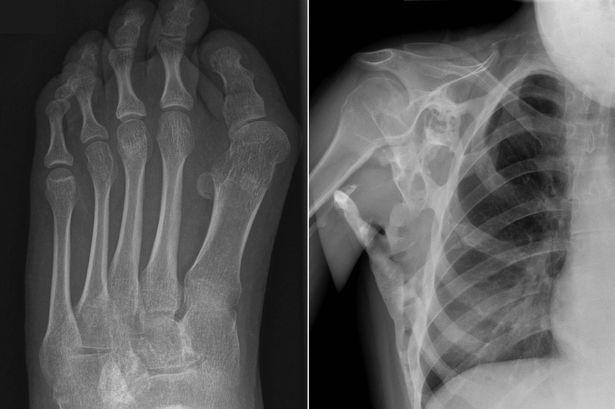

Erken teşhis önem arz etmektedir. Doğuştan deforme hale gelmiş ayak başparmağının varlığı ise belirti niteliğindedir. Bu belirtiye sahip kişiler öncelikle kemik taraması, röntgen, genetik testlerini vb. yaptırması gerekir.

- Eklemlerin kısıtlı hareketleri, genellikle ilk başlarda boyun ve omuzlar.

- Anormal derecede kemik büyümesinin vücut şeklinize yansıması.